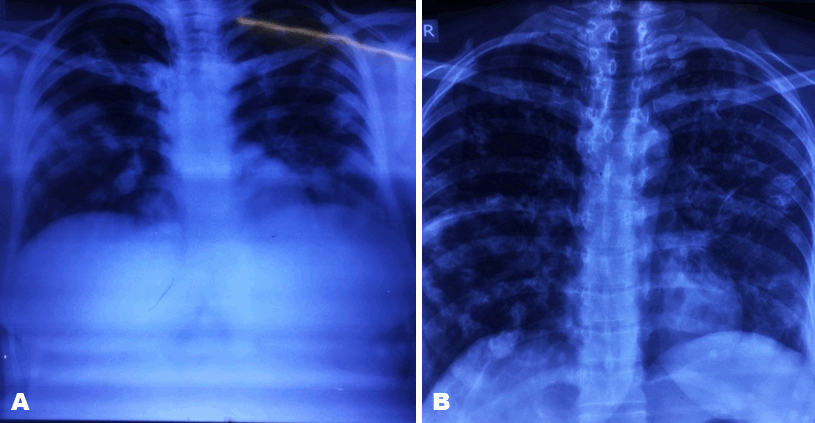

Ultrasonography of abdomen and echocardiography were normal. However, electrocardiography showed sinus tachycardia. The chest radiograph showed bilateral patchy shadows with mild bilateral pleural effusion (Figure 2).

Figure 2: (A) Chest X-ray at the time of admission, and (B) Chest X-ray at the time of discharge.